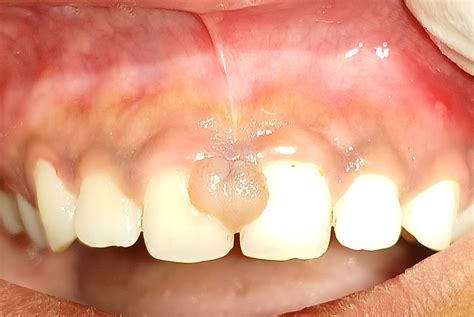

- Fibroma: Es un crecimiento benigno del tejido conectivo en las encías. Suele ser indoloro y puede ser causado por irritación o trauma constante.

Fibroma Oral: Características y Diagnóstico

El fibroma oral es una masa de tejido fibroso que puede desarrollarse en varias áreas de la cavidad bucal. Aunque su origen preciso no siempre es claro, ciertos factores como la irritación crónica, el estrés mecánico o la presión constante pueden contribuir a su formación.

Apariencia y sensación: Se presenta como una masa sólida y firme, a menudo con una apariencia rosada o similar al color de las encías.

El fibroma bucal, también conocido como fibroma traumático o fibroma irritativo, es una lesión benigna de tejido conectivo caracterizada por una proliferación focal de fibroblastos y colágeno. Se presenta como una masa nodular bien delimitada en la mucosa oral y, habitualmente, aparece como respuesta adaptativa del tejido blando de la cavidad bucal frente a un estímulo irritativo crónico.

El fibroma bucal se manifiesta clínicamente como una lesión nodular de tamaño variable que puede oscilar entre los 5 mm y los 2 cm de diámetro.